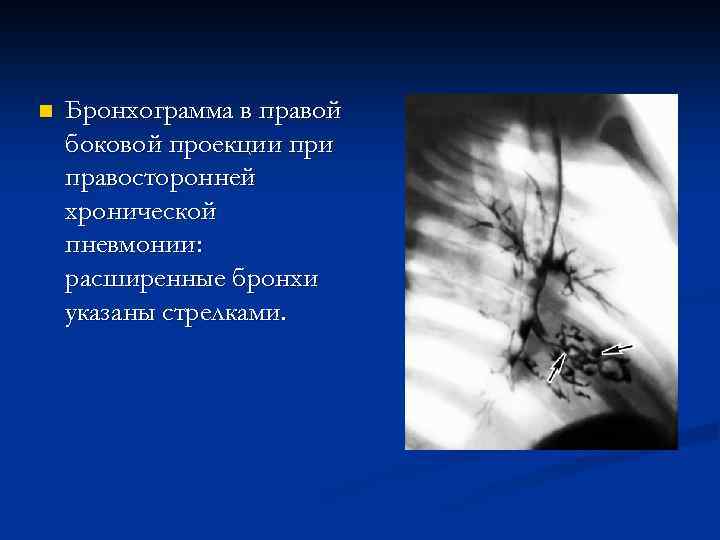

n При бронхографии и компьютерной томографии при хроническом воспалительном процессе выявляется деформирующий бронхит и нередко бронхоэктазы. Деформирующий бронхит выражается неравномерностью просвета (чередованием участков сужения и расширения), неровностью контуров, обрубленностью бронхиальных ветвей, сближением бронхов.

n Бронхограмма в правой боковой проекции правосторонней хронической пневмонии: расширенные бронхи указаны стрелками.